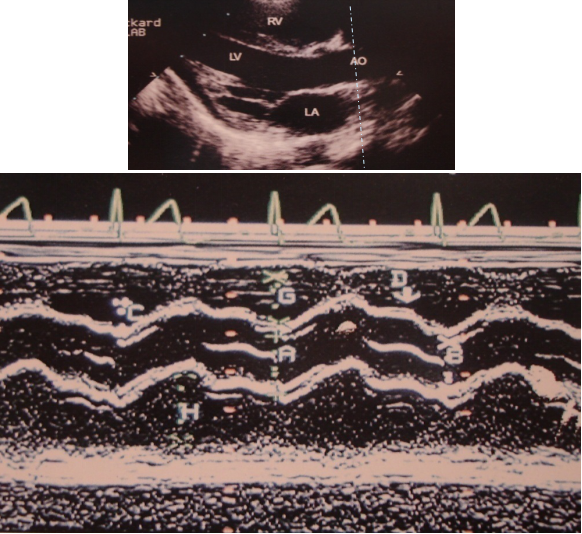

M型超声心动图

二维超声心动图

胸骨旁长轴切面 四腔心切面